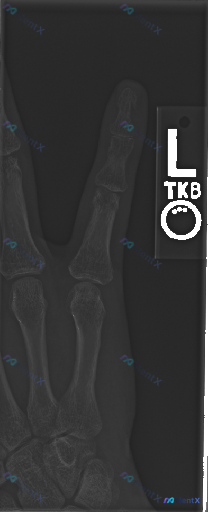

整理了一份左手局部X线的影像资料,先问个直接的:这张图像里能观察到什么明确的异常吗? 补充背景:影像显示的是左手(标注L)食指和中指的正位片,包括完整指骨、对应的掌骨头及部分腕骨。目前影像科的初步评估是“解剖结构基本正常”——骨皮质连续、骨小梁均匀、关节间隙清晰,也没有明显的软组织肿胀或异物。 但想...